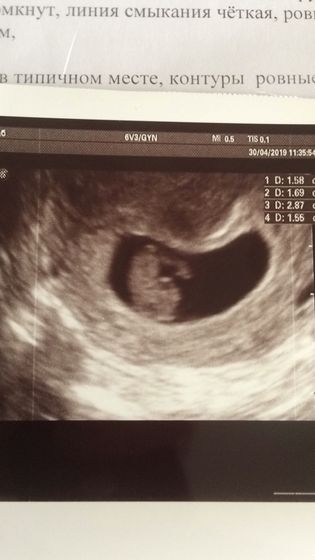

Сходила на узи посмотреть, что там с моей отслойкой) ровно неделя прошла. Отслойка была 18х5 мм, стала 15х5 мм и уплотнилась. Врач сказала возможно и не буду кровить) По остальному соответствуем сроку: свд был 18 мм, стал 28; ктр был 10 мм, стал 15,5 мм☺️растёт моя радость. Есть небольшой тонус правда(

Он вверх ногами ?? головка внизу

Ага?неделю назад ещё не видно было человечка, так… палочка с кружочком ?а сейчас уже заметно